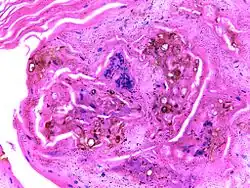

Renal cell carcinoma | Micrograph of clear cell renal cell carcinoma showing cells with clear cytoplasm, typically arranged in nests and nuclear atypia. | Category: Histopathology of renal cell carcinoma | Renal cell carcinoma |

| Cresenteric glomerulonephritis | Photomicrograph of the renal biopsy showing prominent fibrocellular crescent formation and moderate mesangial proliferation in a glomerulus. | Category: Histopathology of glomerulonephritis | glomerulonephritis | |